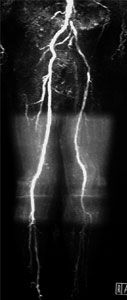

症例10

58歳 男性

両下肢間歇性跛行

平成8年頃より両下肢間歇性跛行(400m)出現。

平成18年4月、当院循環器内科にてPCI施行。

その際の下肢動脈造影にて右EIA狭窄と両側SFAのCTOを認めた(Lt>Rt)。

6月当院紹介受診。

【既往歴】

49歳 肺リンパ腫(化学療法)

高血圧(+) 糖尿病(+) 喫煙歴(−)

ABI:右 0.59 左 0.59

【治療計画】

当日 皆さまと決めましょう

MRA